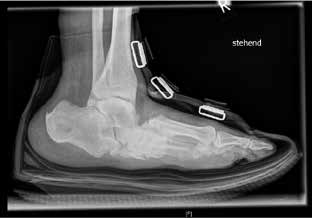

Die Verfasser versorgen den Patienten postoperativ mit einer individuell nach Gipsabdruck angefertigten Unterschenkelorthese. Diese hat ventral eine geschlossene Tibiaanlage, die eine rotationsstabile Ruhigstellung des Fußes ermöglicht. Mit passgerechter Orthese ist eine Vollbelastung des Fußes möglich. Eine solche wird zum frühestmöglichen Zeitpunkt angestrebt, um eine weitere knöcherne Demineralisierung der betroffenen Seite sowie eine Überlastung der kontralateralen Extremität zu vermeiden. Die Belastungsdauer sollte sukzessiv gesteigert werden. Die Verfasser empfehlen, dass die Abnahme der Orthese stets durch den Verordner bzw. in diesem Fall durch den Operateur erfolgen sollte. Erst die Kombination aus adäquater Operation und geeignetem Hilfsmittel macht das Behandlungskonzept aus Sicht der Verfasser erfolgreich. Bei guter Stellung und ausreichender Stabilität des Fußes ist nach ca. 3- bis 12-monatiger Tragedauer der Unterschenkelorthese die Versorgung mit orthopädischen Maßschuhen möglich. Auch hier empfehlen die Verfasser, dass die Abnahme der orthopädischen Maßschuhe durch den Operateur erfolgen sollte. Dabei erfolgt die radiologische Kontrolle im Schuh und im Stehen (Abb. 6). Die Verfasser führen regelmäßige klinische und radiologische Kontrollen in den ersten 2 Jahren durch. Die Kontrollintervalle erfolgen, abhängig vom klinischen Bild, alle 6 bis 12 Wochen. Die Kontrollen in diesem Behandlungszeitraum ermöglichen das frühzeitige Erkennen von Problemen (z. B. neue Ulzerationen oder Druckstellen, neu aufgetretene Schmerzen). Ab dem 3. Jahr können die klinischen Kontrollen halbjährlich erfolgen. Radiologische Kontrollen erfolgen fakultativ.